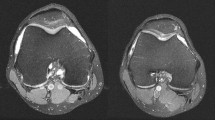

The thickness and width of individual parts of the meniscus were also measured as the parameters of morphological change, and were compared using the methods of Samoto et al. [23] and Ahn et al. [3], modified according to Lee et al. [14]. This procedure was chosen to determine whether the overcorrection during HTO, followed by a shift in the pressure load to the lateral compartment, led to a morphological change in the meniscus. The rationale behind this was that the meniscal tissue has a systemic influence on osteoarthritis [8], so changes in the tissue, such as a reduction in thickness, could lead to forced osteoarthritis. For this purpose, the absolute thickness and width of the pars intermedia and the anterior and posterior horns were measured at their midpoints.

The parameter ‘absolute meniscal width’ was defined as the narrowest point of the external meniscus in coronal view. The parameters ‘absolute meniscal width of the anterior horn’ and ‘absolute meniscal width of the posterior horn’ were recorded in sagittal view, at the point at which the external meniscus was thickest.

To obtain comparable relative values, the relative meniscal width was calculated as a percentage of the maximum tibial width (the maximum extent of the tibia in coronal view, measured from the corticalis to corticalis).

We used a similar approach to estimate the maximum thickness of the anterior horn and posterior horn. To obtain the relative meniscal widths at the anterior horn and posterior horn, the corresponding relative values were calculated as percentages of the maximum meniscal diameter in the sagittal plane.

To determine the absolute meniscal thickness of the pars intermedia, we used a coronal image. In this image, the thickness of the outer meniscus was measured at the point of its maximum vertical extent. Correspondingly, the anterior meniscal thicknesses at the anterior and posterior horns were also determined in the same images.

The relative meniscal thickness and width at the pars intermedia was calculated as a percentage of the maximum tibial width, and the relative meniscal thicknesses and widths at the anterior and posterior horns as percentages of the maximum diameter of the meniscus (Fig. 1).

Measurement of the morphological parameters of the lateral meniscus on MRI. A coronal MR image was used to define the relative meniscal thickness and width at the pars intermedia. a Tibial width (mm); b absolute meniscal thickness at the pars intermedia (mm); c absolute meniscal width at the pars intermedia (mm). Relative meniscal thickness at the pars intermedia (%) = B/A × 100; relative meniscal width at the pars intermedia (%) = C/A × 100. A sagittal image was used to define the relative meniscal thickness and the width at the anterior and posterior horns. d Maximal meniscal diameter (mm); e absolute meniscal thickness at the anterior horn (mm); f absolute meniscal thickness at the posterior horn (mm); g absolute meniscal width at the anterior horn (mm); H: absolute meniscal width at the posterior horn (mm). Relative meniscal thickness at the anterior horn (%) = E/D × 100; relative meniscal thickness at the posterior horn (%) = F/D × 100; relative meniscal width at the anterior horn (%) = G/D × 100; relative meniscal width at the posterior horn (%) = H/D × 100